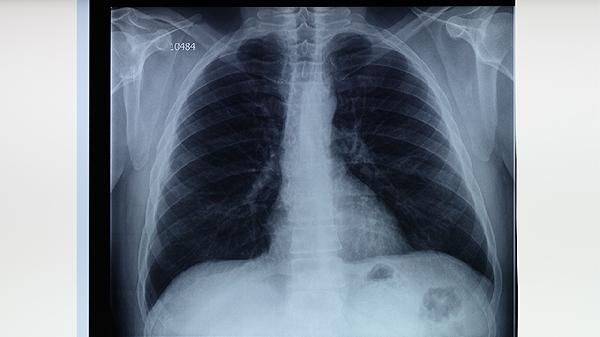

康复期间保持规律作息和良好心态同样重要,可适当补充复合维生素和益生菌。日常饮食注意增加富含锌元素的食物如牡蛎、坚果,有助于促进病灶修复。建议每3个月复查胸部影像学,确保病情持续稳定后再逐步过渡到常规减重模式。